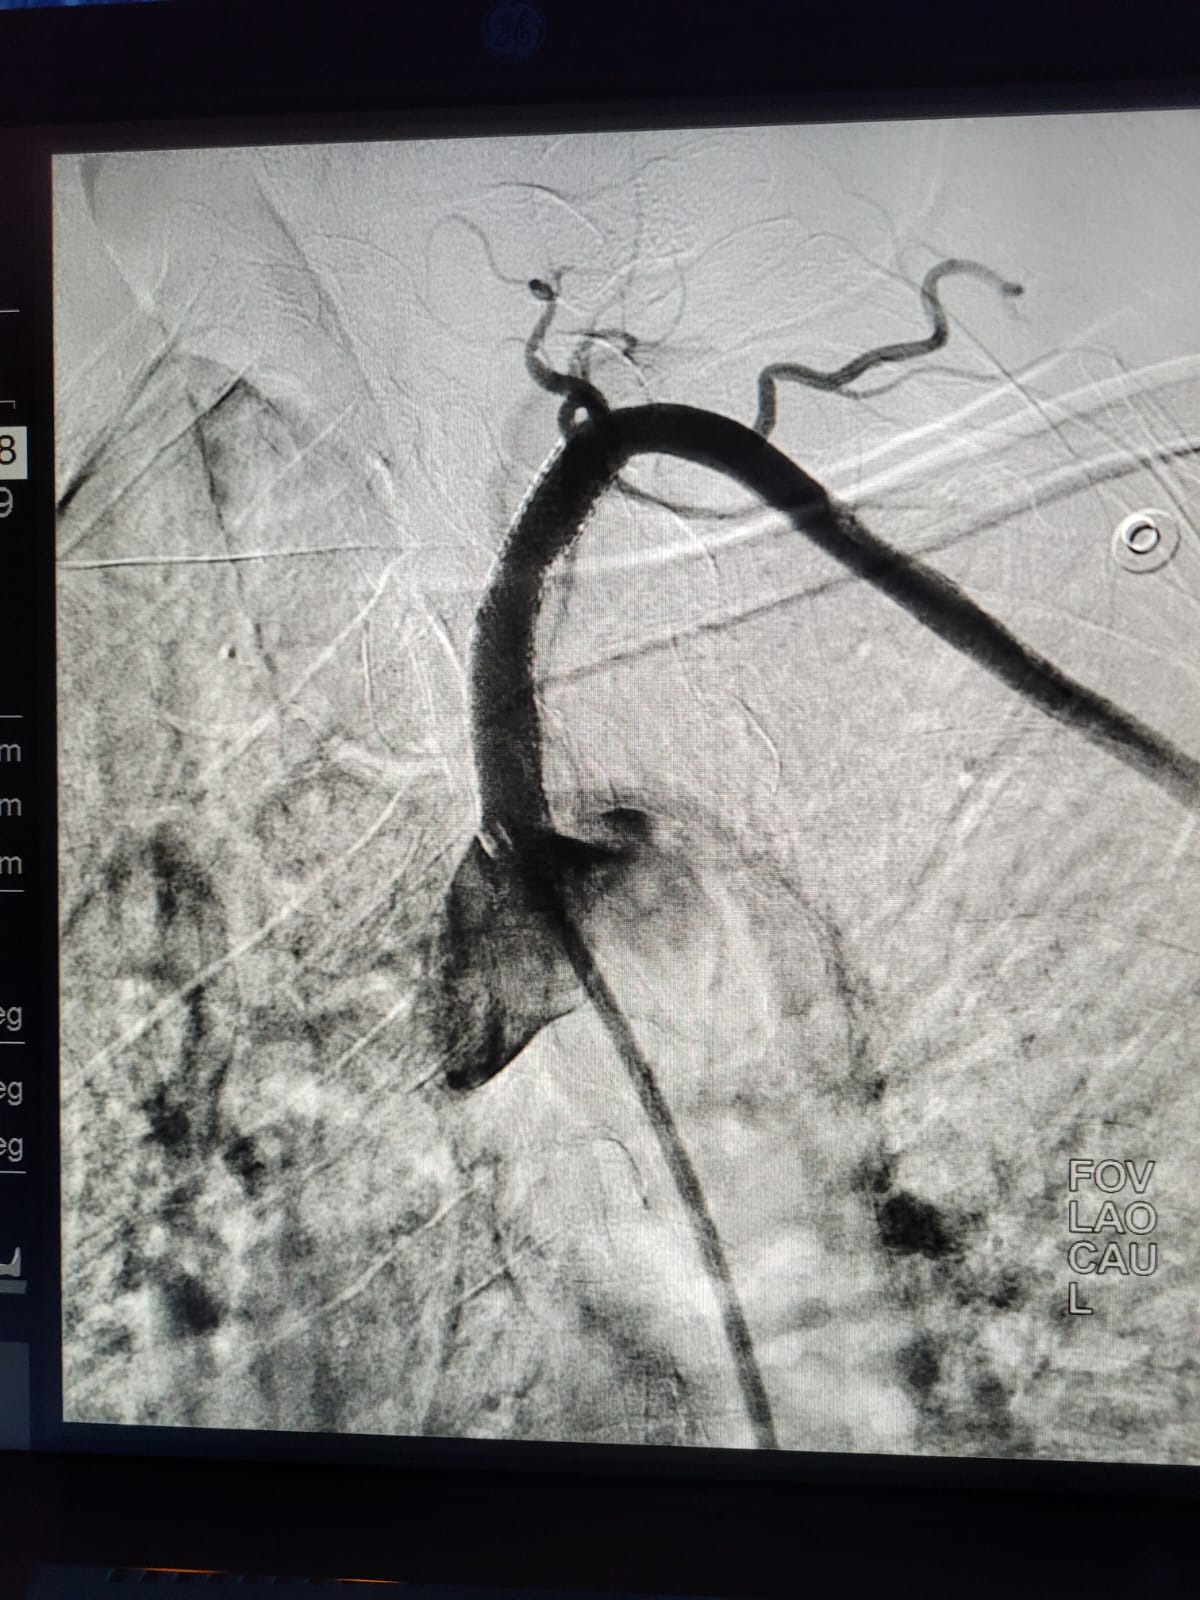

Emergency and Difficult Coronary Angiography / Angioplasty